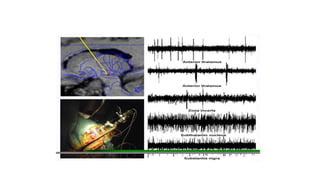

Physiological mapping

.

• S it1) Magnetic resonance imaging

(x, y & z co-ordinates)

2) Intraoperative microelectrode recordings

(neurophysiological localization of target site)

3)Microstimulation

4)Macrostimulation with DBS electrode.

(stimulation of

Physiological mapping . • Sit1) Magnetic resonance imaging (x, y & z co-ordinates) 2) Intraoperative microelectrode recordings (neurophysiological localization of target site) 3)Microstimulation 4)Macrostimulation with DBS electrode. (stimulation of